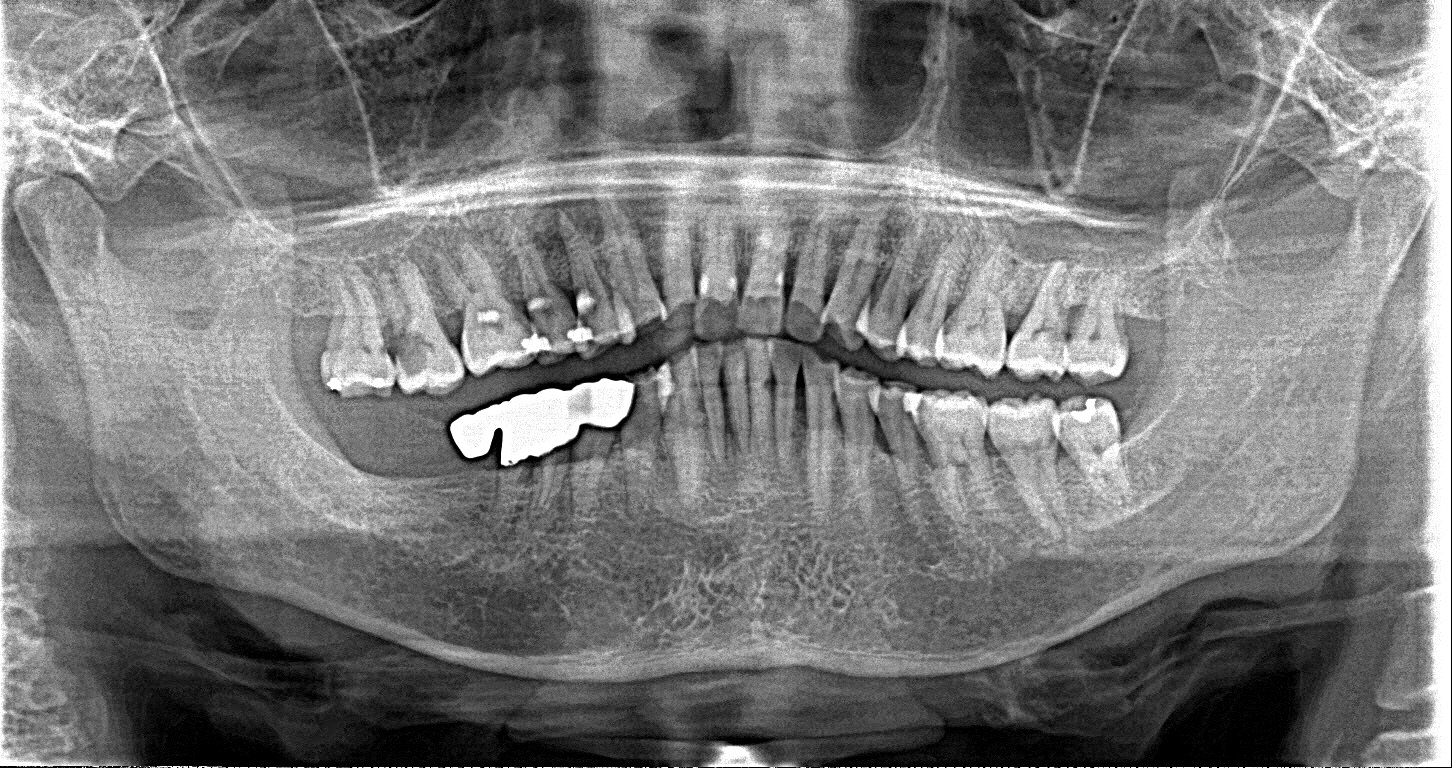

この患者様は、右上の奥歯の歯茎から出血してくるとのことで来院されました。歯周組織検査とレントゲンで診断を行った結果、重度の歯槽膿漏が認められ、保存不可能の為、抜歯になると伝えたところ、入れ歯は絶対に嫌だと言われたので、インプラント治療となりました。CT撮影を行ったところ、上顎洞底までの距離が3ミリ程度しかなかったのですが、骨が固く、フィクスチャーの一次固定が良好だったので、開窓法による上顎洞底挙上術とフィクスチャーの埋入を同時に行いました。約10カ月後に二次手術を行い、上部構造をセットしました。また、右下の臼歯部のブリッジにも大きな二次カリエスが認められ、7番の遠心根が抜歯になり、6番、7番にインプラント治療をしました。

■術前パノラマ